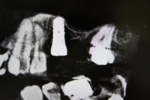

サイナスリフト(骨移植)併用インプラント埋入

ご覧の通り全く骨がないので骨を造りインプラントを埋入しました。

隣の歯も状態が良くなく予後が悪そうです。

抜歯後はインプラントをご希望でしたので、サービスで同部にも骨を移植しておきました。

これで次回オペ時の患者さんの移植のリスクが軽減しました。